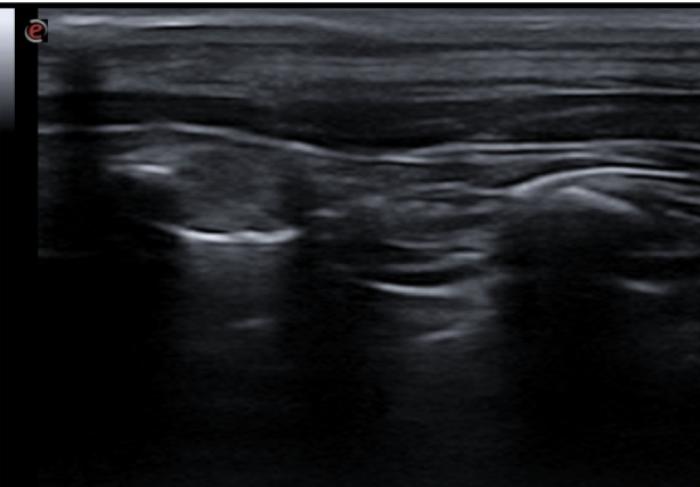

Signo de cuña

Se trata de una consolidación de aspecto triangular o trapezoidal cuya base se encuentra en la LP. Los bordes son más regulares que en el caso del signo de fragmentación, no presentan broncogramas aéreos y si es factible utilizar el Doppler veremos ausencia de flujo en el foco afectado. Comúnmente pueden ir asociados a efusión pleural y si el cuadro respiratorio es agudo, la causa más frecuente es el tromboembolismo pulmonar.

Existe cierta controversia con respecto a si en perros y gatos este signo se describe con aspecto triangular como ocurre en los humanos, puesto que anatómicamente hay diferencias con respecto a la sección menos triangular que describe la vasculatura y por tanto quizá sea más correcto hablar de un aspecto trapezoidal del área consolidada (como se visualiza en la figura 15.3) que puramente triangular (Figura 15A-D).